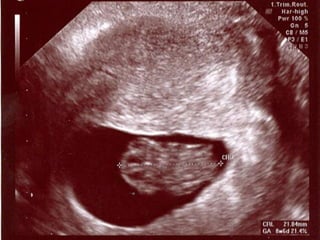

 1. trimesterde (CRL) 2-3 gün hata ile

gestasyonel yaş tesbit edilir